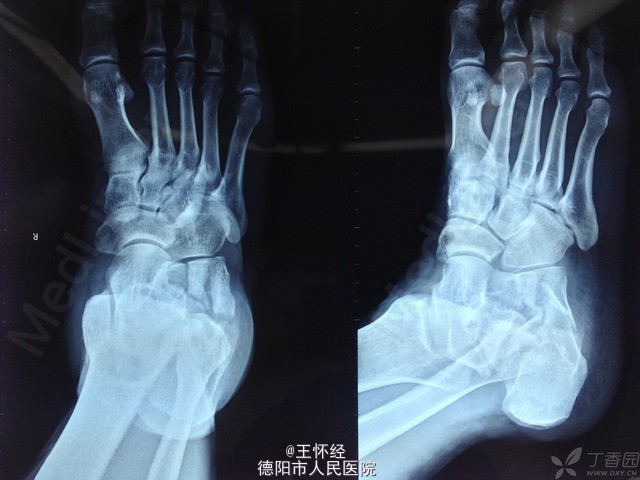

跟骨骨折

患者男性,49岁,车祸伤导致跟骨骨折,入院后完善常规检查,急诊手术。